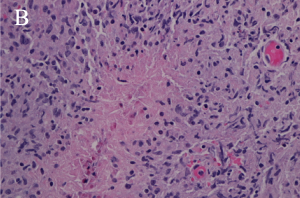

Necrobiotic xanthogranuloma (NXG) is a rare autosomal recessive metabolic storage disorder affecting bile acid synthesis. Ocular manifestations include xanthelasma palpebarum, which may have a necrotic aspect, as well as orbital masses and ocular inflammatory conditions (Images 4A, 4B, and 5).

Xanthogranulomas differ from xanthomas by the presence of Touton giant cells, a type of multinucleated giant cells with high lipid content, and areas of necrosis (Images 3A, 3B, 4A, 4B).